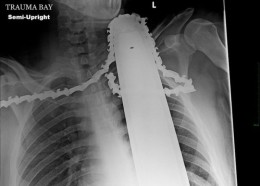

Чудни ренгенски снимки